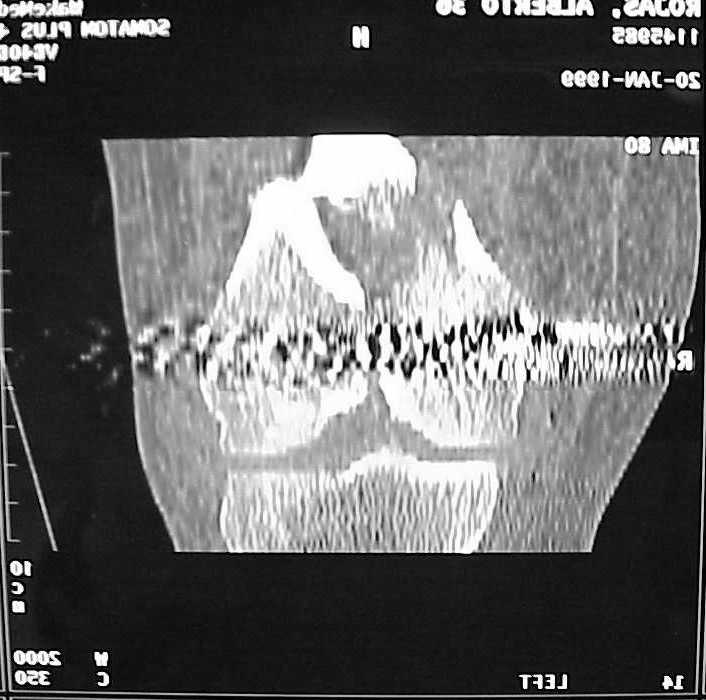

So I think a TAC of the knee could be useful.

A CT and knee xrays would help identify lateral condyle comminution and/or a "hoffa fragment" of the posterior condyle. I am concerned that the lateral cortex is not sufficient to give purchase for a retrograde IMN. blocking screws could improve this as a possibility. A long blade or LISS if avaible would be my secondary choices. Good luck. Any chance you can get these cases transferred earlier when it

Насчет стабильности для ранней нагрузки, конечно, сомнительно, но при таком повреждении ранняя нагрузка противопоказана в любом случае. Для ранних движений Должно хватить. Снимки в следующем сообщении.